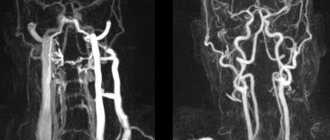

МРТ сосудов шеи

МРТ сосудов шеи Магнитно-резонансная томография ― один из наиболее современных и информативных методов диагностики